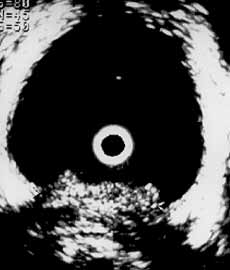

Рис. 7 и 8. Цистэндосонограммы. (Слева) Рак мочевого пузыря с врастанием в интрамуральный отдел мочеточника (стрелкой указан расширенный мочеточник). (Справа) Рак шейки матки с врастанием в мочевой пузырь.